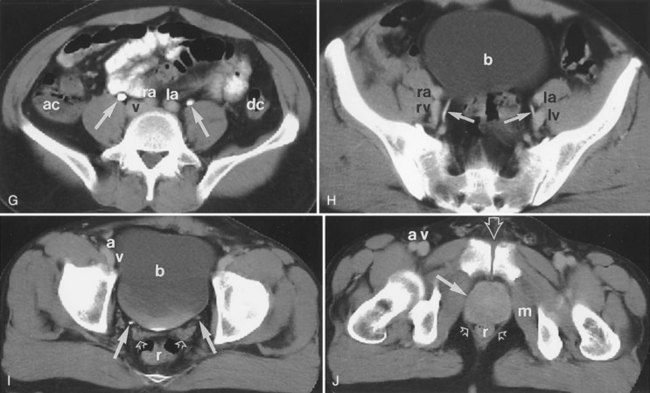

The patient is positioned supine. An abdominal plain radiograph is obtained before the introduction of contrast material (Fig. 4–8A). A commonly employed technique is to insert a small-gauge catheter into the ostomy of the loop, advancing it just proximal to the abdominal wall fascia. The balloon on such a catheter can then be inflated to 5 to 10 mL with sterile water. By gently introducing contrast through the catheter, the loop can be distended, usually producing bilateral reflux into the upper tracts. Oblique films should be obtained in order to evaluate the entire length of the loop (Fig. 4–8B). Because of the angle at which many loops are constructed, a traditional anteroposterior (AP) view will often show a foreshortened loop and could miss a substantial pathology. A drain film should be obtained (Fig. 4–8C). This may demonstrate whether there is obstruction of the conduit.

Figure 4–8 Loopography in a patient with epispadias/exstrophy and ileal conduit urinary diversion. The plain film (A) shows wide diastasis of the pubic symphysis. After contrast administration via a catheter placed in the ileal conduit, free reflux of both ureterointestinal anastomoses is demonstrated (B). A postdrain radiograph (C) demonstrates persistent dilation of the proximal loop indicating mechanical obstruction of the conduit (arrows).